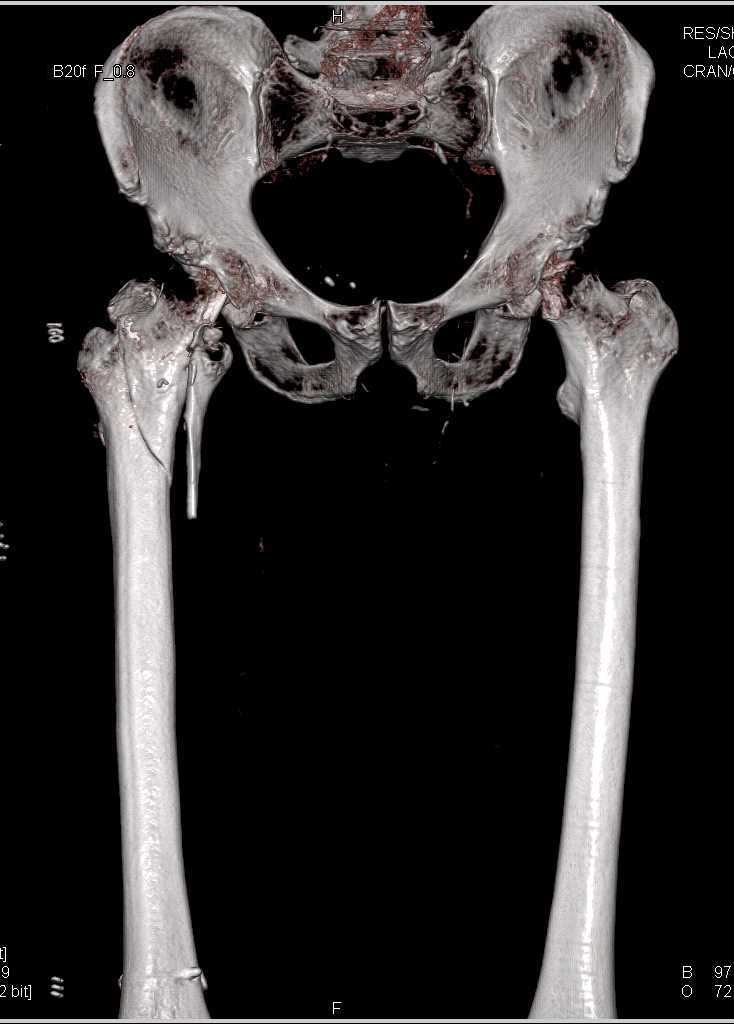

Aneurysm of the Celiac Artery